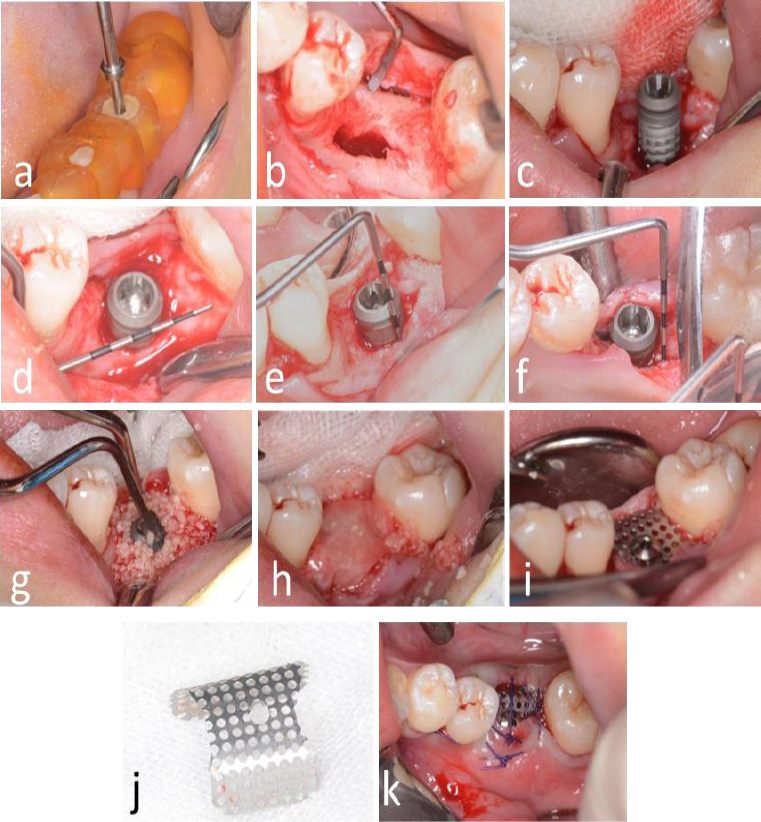

Local anesthesia (Scandonest 2%, Septodent, Saint-Maur-des-Fosses Cedex, France) was administered for hemostasis. The implant surgical guide template and a novel computer-assisted drill guide template were applied to confirm the implant site (Fig. 3a).

A mid-crestal full-thickness incision was created and extended to teeth 45 and 47 through an intrasulcular incision. Two vertical incisions were performed to prepare a trapezoidal mucoperiosteal flap. The flap was elevated on both the buccal and lingual sides to expose the alveolar crest of the molar space. The depth of the implant socket was 13 mm and confirmed by a guiding drill (the occlusal surface was flush with the crest of the adjacent buccal alveolar ridge) (Fig. 3b).

The implant socket was prepared using osteotomes. A periodontal probe was used to check the integrity of the bone wall, and granulation tissue in the implant socket was completely removed.

Bleeding points (decortication) were created using a round bur to expose the underlying marrow of the alveolar crest. The implant socket was filled with bone material (Bio-Oss, Geistlich, Switzerland). Subsequently, the implant (BASIC 4.5×13 mm) was implanted with a torque of 25 N·cm. A periodontal probe was used to examine the exposure of the implant, with 4 mm on the buccal side and 2 mm on the lingual side (Fig. 3c-i).

The titanium mesh was customized according to the dimensions of the osteogenesis area, measuring 12 mm in height and 22 mm in width. The mesh was trimmed to accommodate the buccal height (10 mm), occlusal surface (8 mm), and lingual side (4 mm). It was then contoured into an “n” shape and trial-fitted to ensure proper adaptation (Fig. 3j). A hole was drilled into the occlusal surface for placement of a modified healing abutment.

2.9. Placement of Titanium Mesh

Bone graft material was applied around the implant neck and the buccal alveolar bone defect. A bioresorbable membrane was then positioned to cover the osteogenesis area and perforated at the implant's using a probe. The titanium mesh was subsequently placed and secured onto the implant using a 0.5 mm modified healing abutment (Fig. 3g-i).

Tension-free closure of the soft tissue using resorbable suturing material (Vicryl 3-0) could not be achieved due to insufficient soft tissue availability. As a result, the titanium mesh remained partially exposed, and a periodontal dressing was applied to protect the surgical site (Fig. 3k).

Surgical procedure for dental implant placement. (a) Positioning of the surgical guide template, (b) Reflection of a trapezoidal mucoperiosteal flap, (c) Osteotomy and implant placement, (d) Peri-implant bone defect at the cervical region, (e) Buccal vertical bone defect measuring 4 mm; (f) Lingual vertical bone defect measuring 2 mm, (g) Augmentation using alloplastic bone graft material, (h) Application of bioresorbable membrane to cover the graft site, (i) Fixation of titanium mesh using a 0.5 mm modified healing abutment, (j) Contouring of titanium mesh prior to placement, (k) Postoperative exposure of titanium mesh.